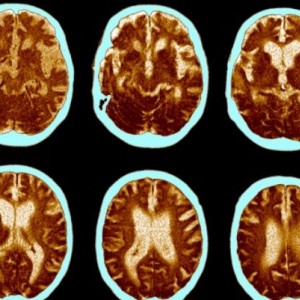

Alzheimer’s is a scary, brutal disease. My mom, and my grandmothers all had it. I’m scared to death of it. I don’t know if it’s in my head because what wouldhave been my mom’s 78th birthday is a few days away, or if it’s coincidental that new studies are hitting the media. Either way, I’m an advocate of research for this problem.

There's new evidence that says it might be reversible, or even preventable. Carbs have a lot to do with it. Read On.